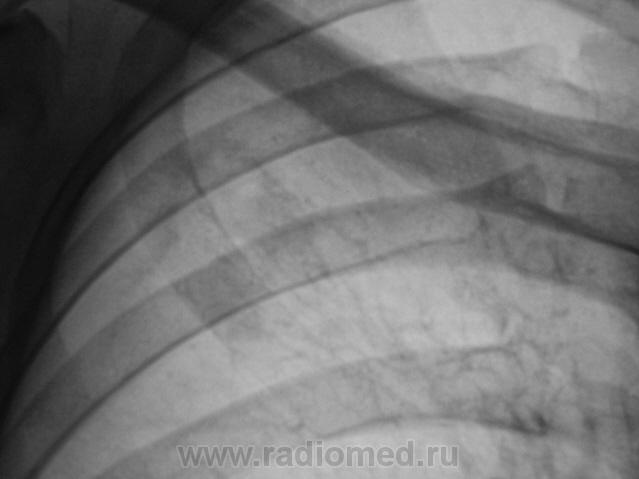

Томограммы.

Я бы остановилась на множественных туберкулемах s1-2 обоих легких,Туберкулемы не однородны.за счет уплотнения,пл очаги.фиброз.

Слева туберкулома и корень подтянут Справа-очаги отсева .Динамика типичная- лечим.лечим-а туберкуломе хоть бы хны!

Туберкулёма только в С1+2 слева, как дела давно минувших дней.  Произошла реактивация туберкулёзного процесса с развитием двустороннего очагового туберкулёза. Имеется положительная динамика в виду некоторого уплотнения очагов. Таково мое мнение.